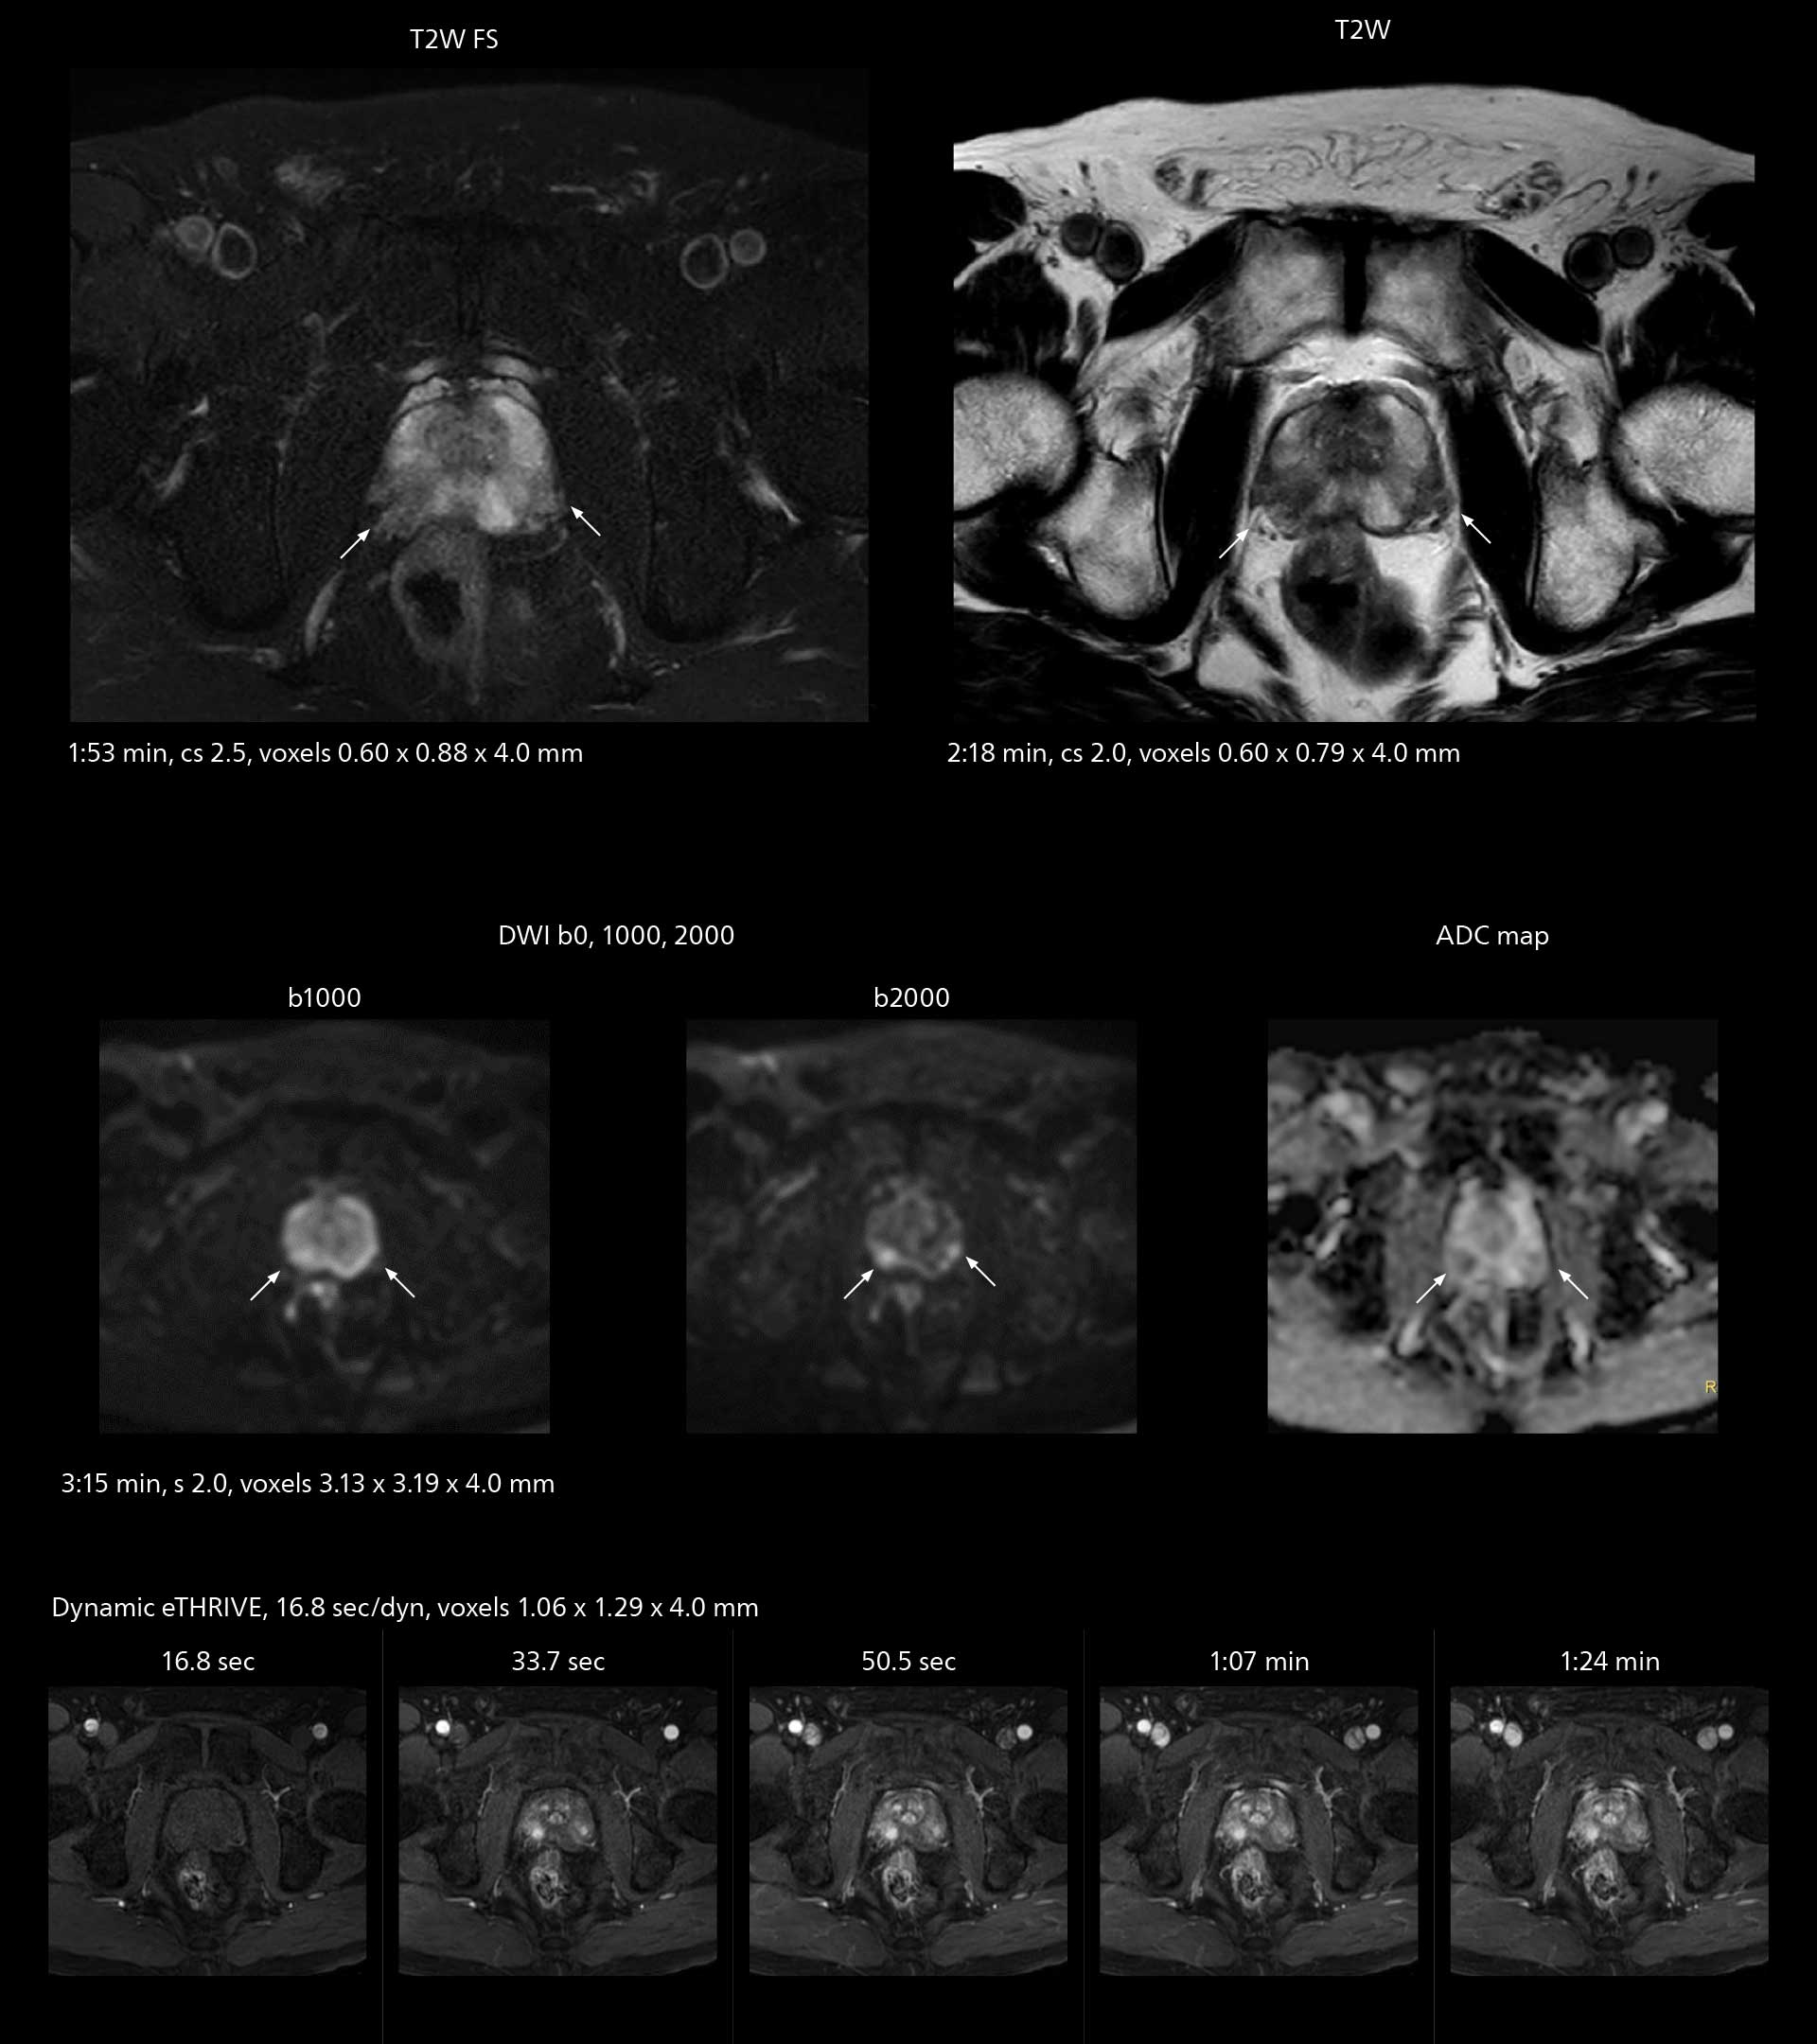

Diffusion studies benefit from powerful gradients

The high performance of the Vega HP gradients is particularly impressive in DWI. “The Vega HP gradients enable us to scan faster and use b-values as high as 2000, for example in prostate DWI and in DWIBS, which provides image quality that is remarkably improved over the previous system and we are able to more easily see lesions.”

MRI of prostate

Examples of prostate imaging showing faster scan times and improved resolution illustrate the power of SmartPath to Elition X in this case of prostate cancer with PI-RADS score 4.

MRI of prostate

Examples of prostate imaging showing faster scan times and improved resolution illustrate the power of SmartPath to Elition X in this case of prostate cancer with PI-RADS score 4.